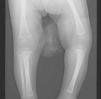

Se realiza punción lumbar: normal. VDRL en LCR, negativo. Radiografías de la serie ósea: reacción perióstica en la región proximal de ambos fémures (fig. 1), a diferencia de la región proximal de ambos húmeros. Reacción perióstica simple continua en ambos fémures y tibias (fig. 2). No se observan lesiones osteolíticas. Ecografía cerebral y cardíaca, normales. En la ecografía abdominal, hepatoesplenomegalia homogénea y en riñones, hiperecogenicidad cortical, sin otras alteraciones. Función glomerular, normal. La aminoaciduria y la hematuria indican tubulopatía, que se resuelve tras 8 meses de aportes orales de bicarbonato sódico. La disfunción hepática se resolvió tras el tratamiento (a partir de las 4 semanas de vida, 200.000–300.000U/kg/día, administrado vía intravenosa cada 6h): bencilpenicilina 250.000UI/kg/día vía intravenosa cada 6h durante 10 días. En la evolución ha presentado caída progresiva de los títulos de RPR. En el último control (a los 15 meses del diagnóstico), RPR positivo a título 1/2. El seguimiento clínico y serológico durante los 6–12 meses posteriores al tratamiento consiste en confirmar el descenso en los títulos de anticuerpos hasta que se negativicen. Los pacientes que presentan títulos elevados persistentes o crecientes deben ser reevaluados (incluida punción lumbar) y se debe considerar retratamiento con bencilpenicilina durante 10 días.